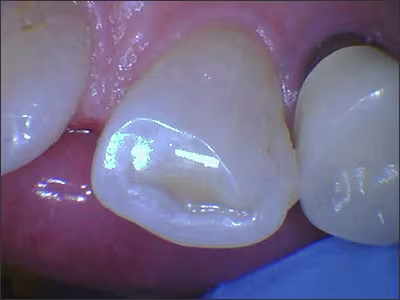

Canines tend to show the first visual signs of bruxism because the anatomy of a canine is longer and more pointed than other tooth types. Wear facets or flat canines are obvious visual signs of grinding (Figure 3). As the canines become shorter and become in line with the occlusal line of the premolars, the force is then shared with the rest of the molars (Figure 4). Signs of attrition on molars start with the cusps flattening out and can even wear through to the dentin.39

Figure 3.

Facial surface exhibiting flattened, smooth, polished enamel wear on tooth #23.